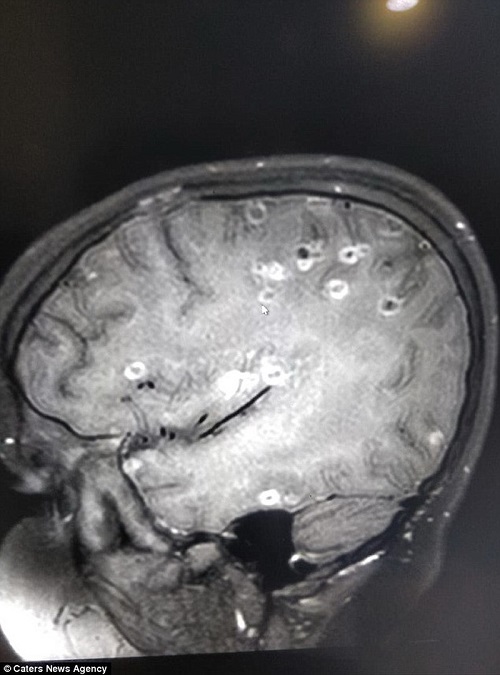

6 tháng sau, gia đình đưa cô bé đến BV Fortis ở Gurgaon. Tại đây, bản phim chụp cho thấy cô bé bị mắc một hội chứng gọi là loạn thần kinh neurocysticercosis. Trong não cô bé có hơn 100 chấm trắng biểu thị cho trứng sán dây.

Phim chụp cho thấy có hơn 100 trứng sán dây trong não cô bé. Ảnh: Daily mail |

Tiến sĩ Praveen Gupta - Trưởng khoa thần kinh tại Bệnh viện Fortis ở Gurga (Ấn Độ) cho biết: “Qua phim chụp, chúng tôi phát hiện não bé gái có 100 trứng sán dây. Cô bé đã vô tình ăn thức ăn bị nhiễm sán dây. Bé liên tục bị đau đầu dữ dội, co giật và động kinh trong 6 tháng qua. Khi nhập viện, cô bé gần như bất tỉnh do u nang và não bị sưng lên”.